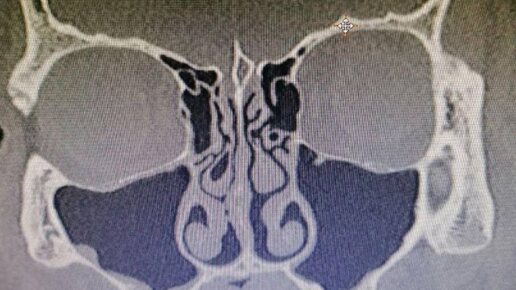

Пазуха в блокаде. Как вылечить хронический гайморит

Гайморит не только значительно снижает качество жизни, но может даже угрожать ей. Как от него избавиться? Наш эксперт — ринохирург Сергей Карпович. У человека несколько придаточных пазух носа. Есть основная — клиновидная, а также лобные и ряд мелких. Эти кост­ные образования похожи на пещерки, сообщающиеся с внутренней полостью носа. Иногда они воспаляются, и тогда возникает синусит, то есть насморк. Гайморит, по сути, — это разновидность синусита, только вызывает его воспаление исключительно верхнечелюстных (гайморовых) пазух носа...